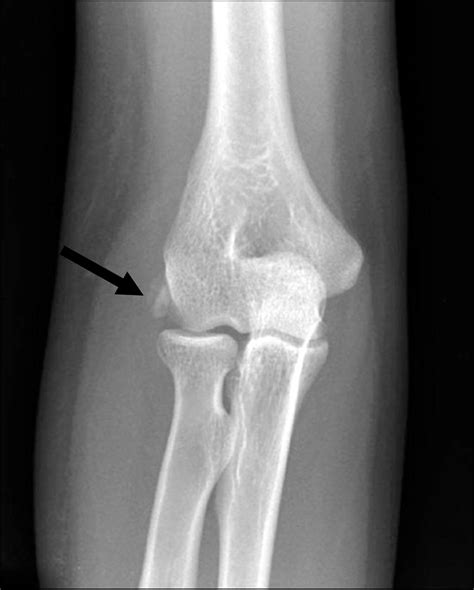

Rotator Cuff Calcific Tendinitis | Images and Photos finder